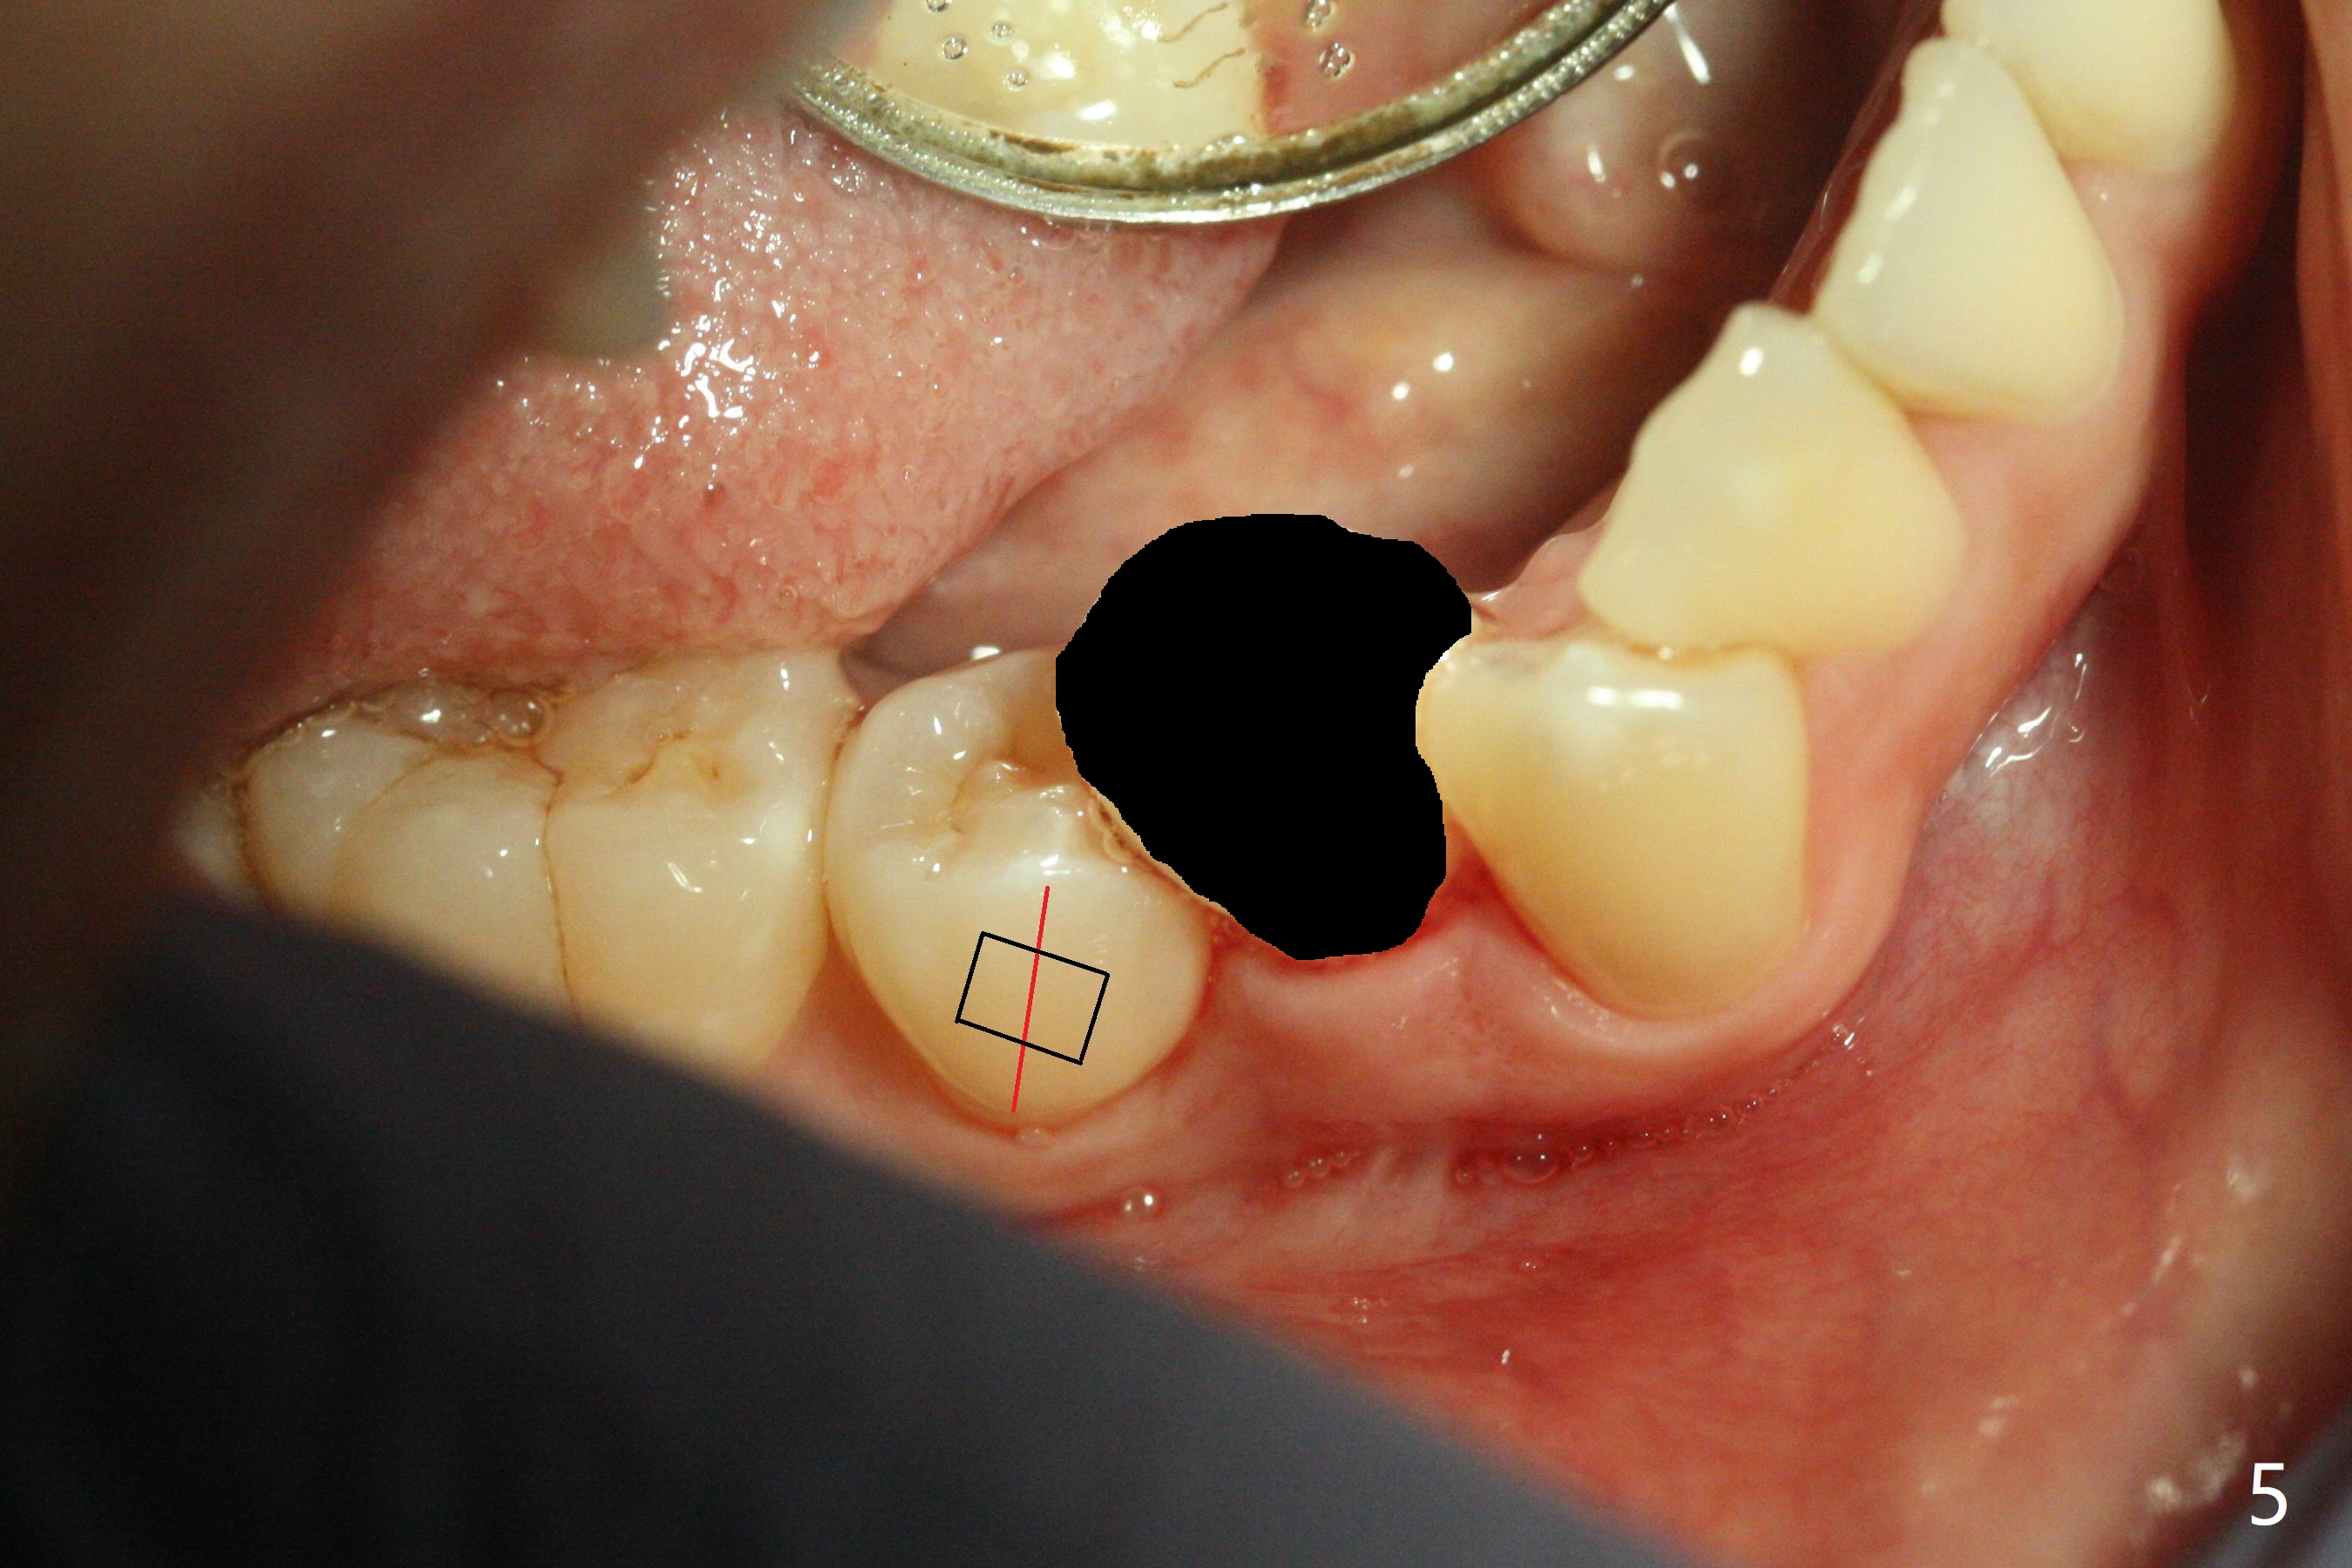

A 34-year-old woman with crowding particularly at LR 4/5 (Fig.1) and suspected DO caries of LR4 (Fig.2) returns with symptom of pulpitis and "cavity" at LR5 (MO). New Bitewing confirms LR4 DO caries (Fig.3). Treatment plan is to extract LR4 and place composite at LR5 if present. Extraction turns out to be difficult because of nervousness and TMD of the patient and crowding. The proximal areas of LR4 requires removal before luxation without traumatizing the neighboring teeth (Fig.4 insert black areas). In fact there is no caries at LR5. When the patient returns for orthodontic treatment, bracketing at LR5 should consider overcorrection (Fig.5 (black rectangle vs. red line: height of contour)) due to the tilted long axis (Fig.1).